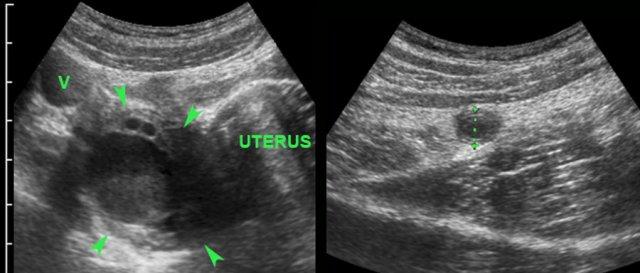

Ở người phụ nữ trẻ này, một nang buồng trứng phải xuất huyết nổi bật (đầu mũi tên) được quan sát thấy và được cho là nguyên nhân gây triệu chứng hố chậu phải.

Tuy nhiên, tìm kiếm thêm đã phát hiện viêm ruột thừa cấp, nang buồng trứng chỉ là phát hiện tình cờ gây nhầm lẫn.